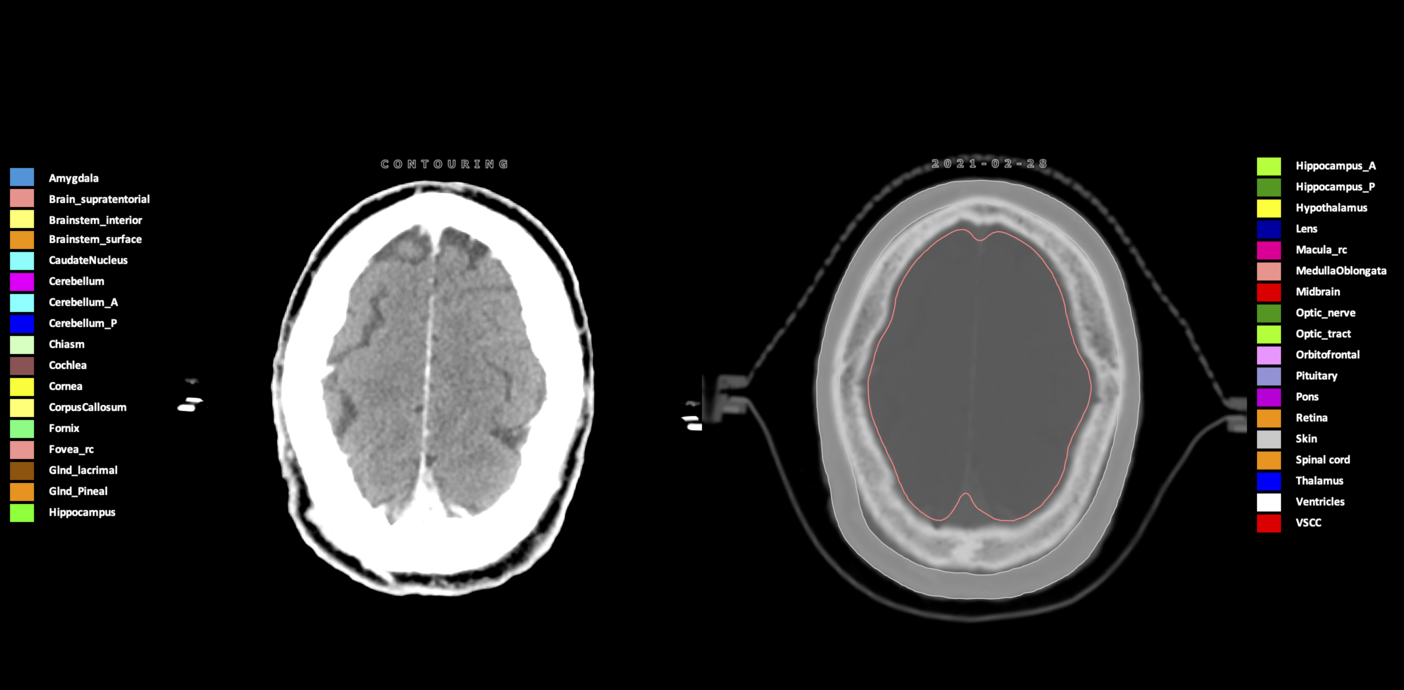

Included are all OARs known to be relevant for radiation-induced toxicity in neuro-oncology: brain, brainstem (midbrain, pons, medulla oblongata), chiasm, cerebellum (anterior & posterior), cochlea, cornea, hippocampus (anterior & posterior), hypothalamus, lens, lacrimal gland, optic nerve, pituitary, skin, and vestibular & semicircular canals. To further facilitate research on cognition, vision and radiological changes after irradiation of the brain, potential clinically-relevant OARs are included: amygdala, caudate nucleus, cerebellum (anterior & posterior), corpus callosum, fornix, macula, optic tract, orbitofrontal cortex, periventricular space (PVS), pineal gland, and thalamus.

Three-dimensional delineation of the 25 consensus OARs for neuro-oncology are shown on CT (WW/WL 120/40, 3000/600), 3T MR images, (T1Gd, T2FLAIR 1mm) and 7T MR (MP2RAGE 0.7 mm). All are presented in transversal, sagittal and coronal view.